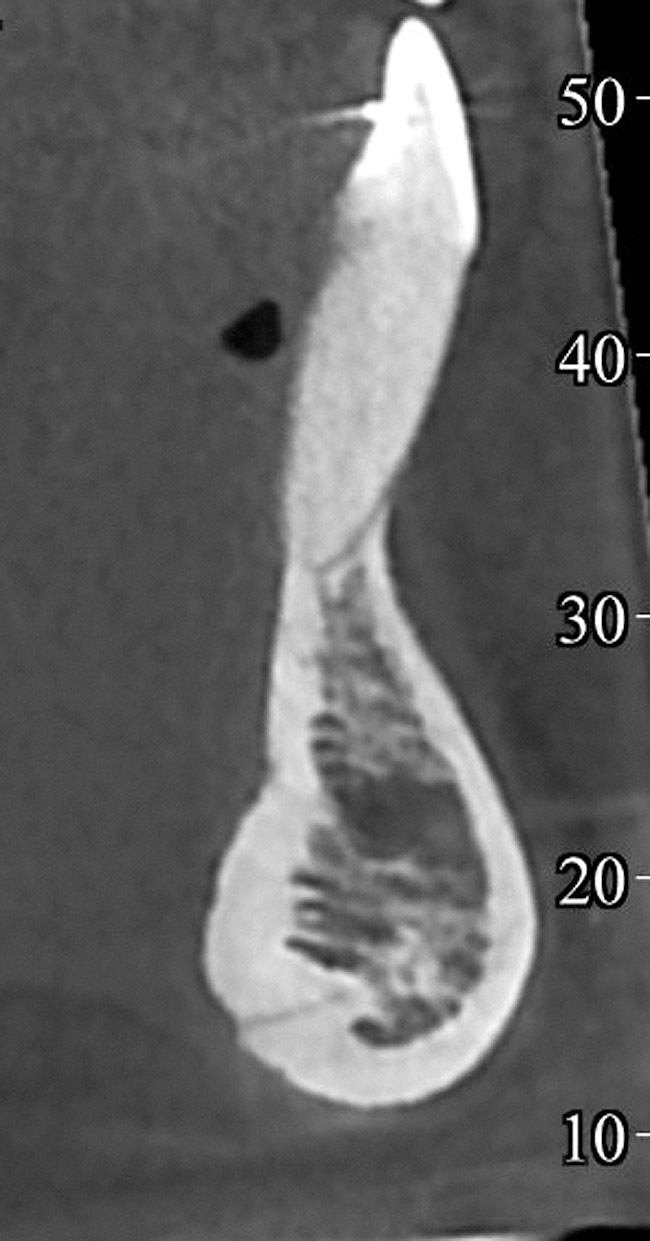

When teeth with GR present with an increased labial root inclination and prominence, orthodontic correction of tooth position should be then considered. The decision about whether orthodontic treatment is possible depends on the thickness of the bone lingual to the affected root. The only modality to accurately assess the labio-lingual thickness of the alveolar bone is cone-beam computerized tomography (CBCT) imaging. Studies that compared measurements on cadavers and CBCT showed that CBCT measurements are an accurate representation of the clinical bone thickness.31-33

Based on these data, a minimum of 2.5 mm of lingual alveolar bone thickness, measured on CBCT views at 8 mm apical to the CEJ, is recommended for orthodontic tooth repositioning of a labially displaced root.

In cases with thin lingual bone, as measured on CBCT (<2.5 mm at a level of 8 mm apical to the CEJ), orthodontic treatment is not advisable, leaving surgical root coverage as the only option. However, the prognosis for this procedure is poorer, because the predominant cause is not addressed. Figure 4 shows the frontal clinical view of a patient with a hyperdivergent growth pattern who presented with post-orthodontic GR of a labially displaced lower central incisor. The sagittal CBCT view (Figure 5) shows complete absence of lingual bone, which contraindicated orthodontic tooth repositioning.

Fig 5. CBCT sagittal view of the same patient showing thin/no bone on the lingual aspect.

Figure 5

Fig 18. CBCT sagittal view shows no bone on the labial aspect and 2.5 mm bone thickness on the lingual aspect.

Figure 18